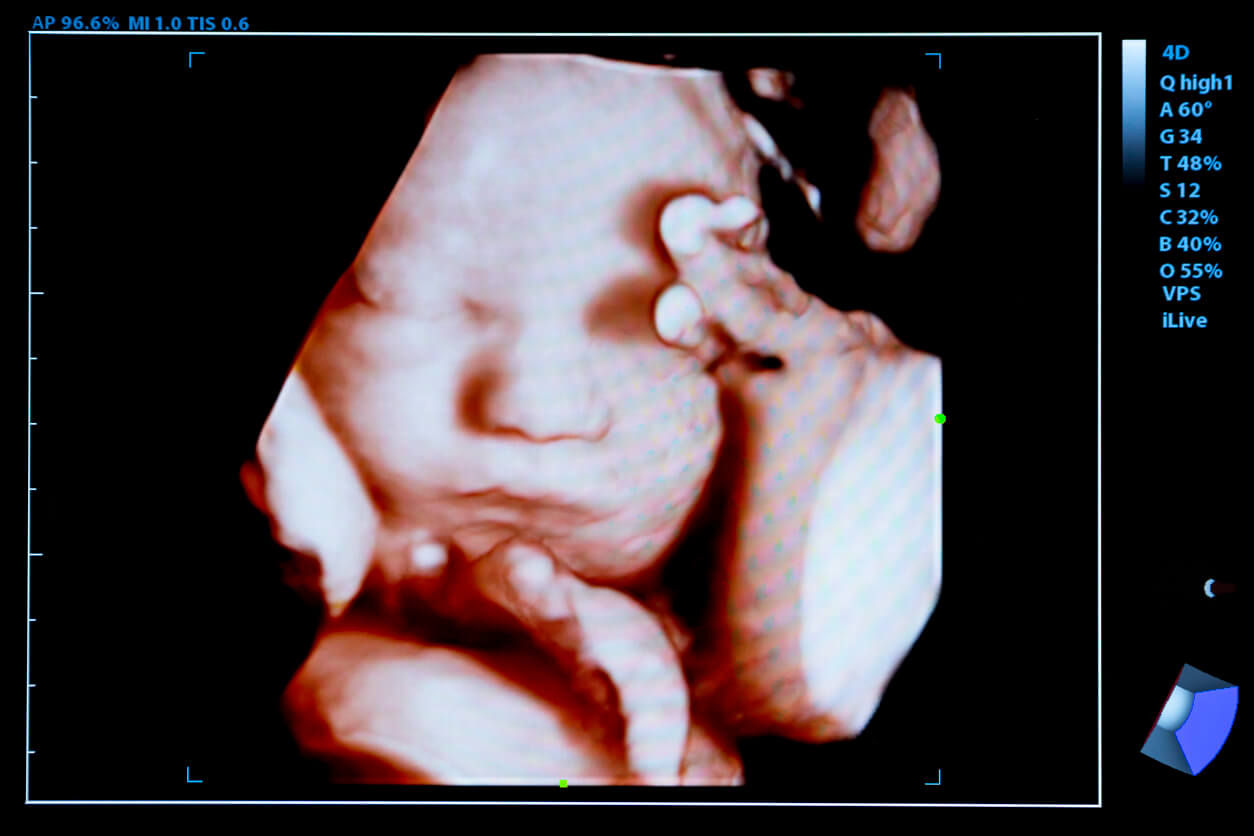

Desenvolvimento da pele fetal

A pele é o maior órgão do corpo, por isso seu desenvolvimento começa no início da gravidez, entre 5 e 8 semanas.

Nas primeiras semanas de gravidez, a pele do bebê é formada por apenas duas camadas: as células basais (que é a camada mais interna) e as células peridermais (que é a camada mais externa). Por volta da nona semana, uma nova camada começa a se formar entre as duas anteriores, de onde sairão os folículos pilosos da pele.

A pele continua com seu processo de desenvolvimento. Assim, no segundo trimestre, todas as camadas que a compõem terão sido formadas. No entanto, durante todo o período de gestação a pele fica transparente devido ao seu baixo teor de gordura corporal.

As glândulas da pele do bebê começam a produzir uma substância semelhante a óleo chamada vérnix caseosa. Essa camada branca e gordurosa é composta de células da pele que foram eliminadas junto com as secreções sebáceas. Além disso, permanece na pele até o momento do nascimento e atua como proteção contra o líquido amniótico e possível maceração.

No terceiro trimestre, os bebês adquirem uma coloração diferente da pele, que deixa de ser tão transparente e engrossa. No entanto, ao nascer, o pequeno terá uma tez roxa, independentemente do tom de pele de ambos os pais. Isso porque o sistema circulatório ainda não se adaptou definitivamente ao meio extrauterino.